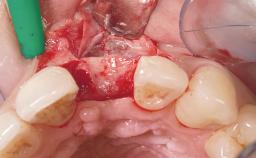

Late Placement of an Implant in a Maxillary Left Central Incisor Site

A 36-year-old female patient was referred for the replacement of the upper left central incisor (tooth 21), which had fractured. Although the tooth had been asymptomatic for many years, the crown began to loosen, at which time she presented to her dentist for an assessment. Teeth 21 and 22 had both been endodontically treated many years previously. She was a healthy individual and a non-smoker.

On examination, the patient had a low lip line and only displayed the coronal half of the anterior teeth when smiling.

The crown of tooth 21 was splinted to the adjacent teeth with composite resin, and the gingiva was inflamed.